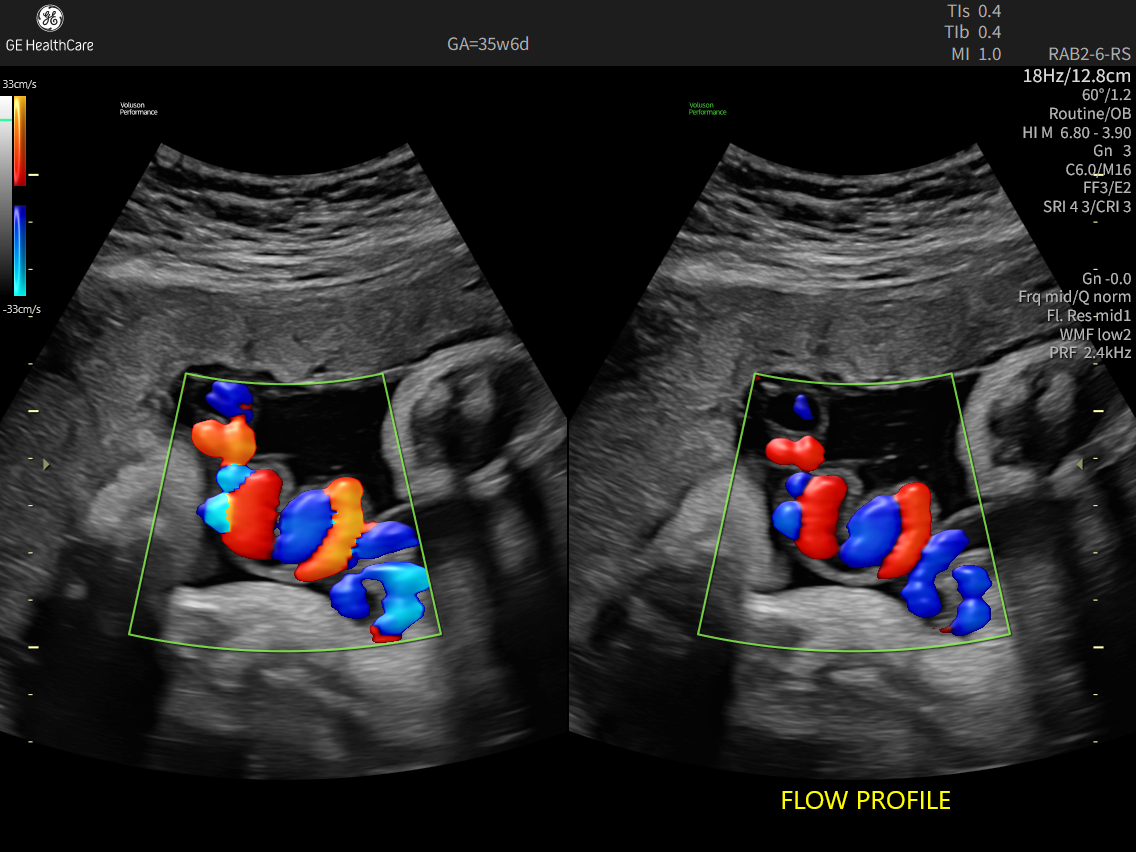

Fast, easy 3D-like blood flow visualization

Go with the flow